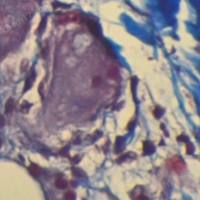

本服务将根据客户需求订制心脑血管、脑神经、肿瘤、关节炎等相关动物模型动物模型及后续评价服务(承接服务的前提是尊重知识产权,具体服务内容及方式待详细协商)。以下为部分工作内容展示: